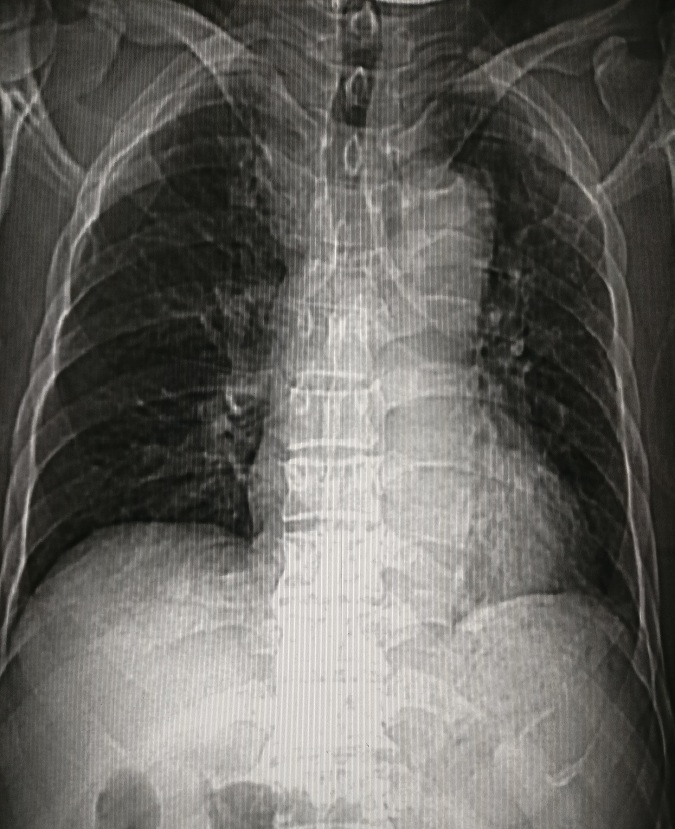

4.右心房增大

主要见于右心衰竭、先心病如房间隔缺损、三尖瓣病变等。见图4。

图4 房间隔缺损,以右房增大为主,右肺动脉干增宽,肺动脉段明显膨隆